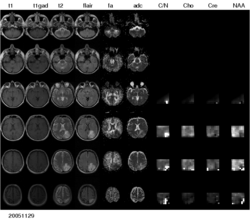

Figure 1: Multi-modal image data from a patient with low-grade glioma. A large number of different modalities and derived parameter volumes are acquired during the monitoring of tumor growth.

We are interested in developing computational methods for the assimilation of magnetic resonance image data into physiological models of glioma - the most frequent primary brain tumor - for a patient-adaptive modeling of tumor growth.